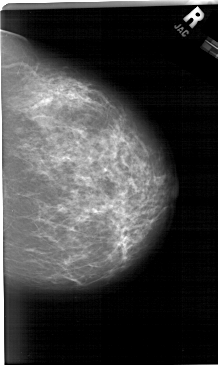

A_1284_1.RIGHT_CC

RIGHT_CC LINES 6571 PIXELS_PER_LINE 3916 BITS_PER_PIXEL 12 RESOLUTION 43.5 NON_OVERLAY